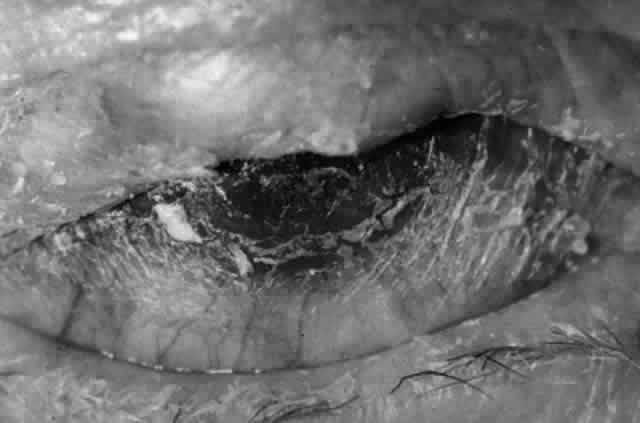

Clinically, the ocular disease in cicatricial pemphigoid (OCP) may present unilaterally in the form of a chronic, recurrent catarrhal conjunctivitis, but it eventually becomes bilateral. Subepithelial fibrosis is characteristic of stage 1 of OCP (Fig. 7). Stage 2 shows fornix foreshortening (Fig. 8), and symblepharon formation is the hallmark of stage 3 (Fig. 9). Stage 4, end-stage disease, is characterized by ankyloblepharon and surface keratinization (Fig. 10). Obstruction of the lacrimal ductules and meibomian gland ducts eventually produces an unstable tear film and progressive sicca syndrome, but it is to be emphasized that OCP is not a dry-eye syndrome until late in the disease course.20 Trichiasis and entropion occur because of the subepithelial fibrosis, with eventual keratopathy, corneal neovascularization, and corneal ulceration and scarring.20

Fig. 10. Stage 4 cicatricial pemphigoid. Progressive shrinkage of the conjunctiva resulted in extreme trichiasis and distichiasis and keratopathy, with compromise of meibomian ductules and lacrimal ductules and the production of a totally dry eye.